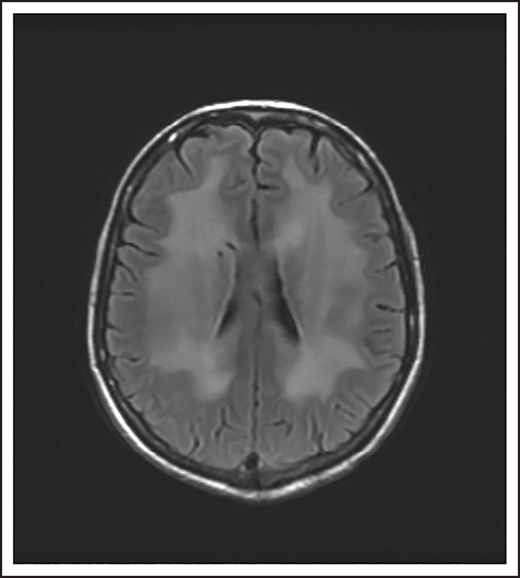

A 74-year-old man with a history of DLBCL treated with R-CHOP presented with progressive confusion and right-side weakness. A brain MRI demonstrated a contrast-enhancing lesion in the corpus callosum with extension into the left parietal region. A biopsy of the enhancing lesion confirmed a diagnosis of DLBCL. No other sites of disease were identified, and he was diagnosed with isolated CNS relapse. He was treated with HD-MTX, rituximab, and temozolomide for 4 cycles, and he achieved a complete radiographic response. Three years later, he presented with progressive memory loss, urinary incontinence, and gait ataxia. A brain MRI demonstrated periventricular white matter T2/FLAIR hyperintensities (Figure 3). Evaluation for toxic and metabolic causes of his symptoms was negative. His diagnosis was MTX-induced leukoencephalopathy.

Brain MRI of a patient with leukoencephalopathy caused by use of HD-MTX. An axial T2 fluid attenuated inversion recovery (FLAIR) image shows periventricular hyperintense signal reflecting leukoencephalopathy.

Antimetabolites

HD-MTX as well as IT MTX can cause acute as well as subacute encephalopathy.57,58 Acute encephalopathy is usually reversible. Subacute, or chronic, encephalopathy, as seen in case 4, is typically progressive, irreversible, and associated with high morbidity and mortality. It is a diagnosis of exclusion and as described in case 4, other causes must be excluded. The risk is higher with older age and when combined with whole-brain radiation therapy (WBRT).59